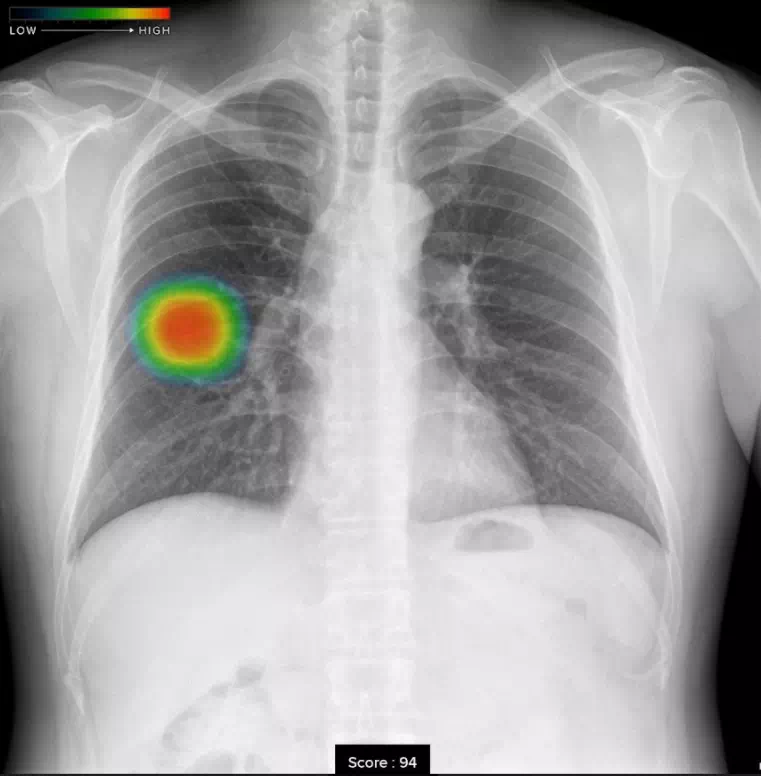

結節・腫瘤影

ヒートマップ表示機能

AIが異常の可能性がある領域を自動解析し、確信度に応じた表示を行います。確信度のスコアは0~100の範囲で設定され、画像上では色分けされたヒートマップとして示されます。

スコア表示機能

0~100の範囲で確信度スコアの最大値が数値として表示されます。